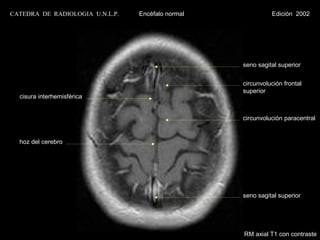

CATEDRA DE RADIOLOGIA U.N.L.P.   Encéfalo normal             Edición 2002

seno sagital superior

circunvolución frontal

superior

cisura interhemisférica

circunvolución paracentral

hoz del cerebro

RM axial T1 con contraste